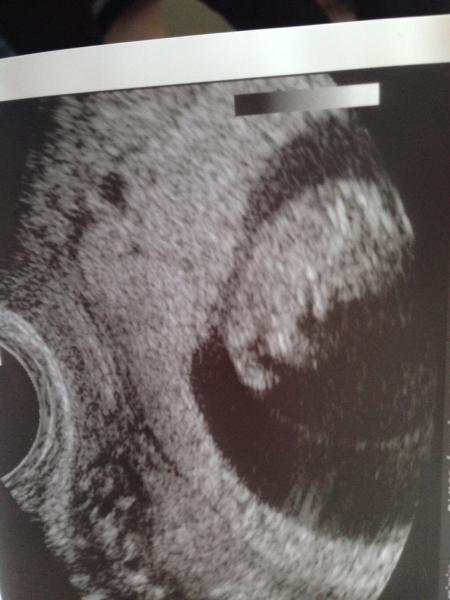

Hallo ihr lieben, ja, ich bin auch froh, dass bei mir die zeitbis zur 12. Woche so langsam vorbei streicht;-) Am Sonntag bin ich endlich offiziell in der 12. Woche und den Samstag darauf, also bei 11+6 werden wir es allen an der Geburtstagsfeier meines Mannes sagen.... Ich bin schon gaaaanz aufgeregt;-) Wir lassen meinem Sohn ein T-Shirt druchen, wo drauf steht: " Großer Bruder Mai 2014". Ich bin seeeehr gespannt, wie die anderen darauf reagieren und was sie dazu sagen;-) und vor allem, wann sie es sehen;-) Ich hin froh, dass meine Angst langsam abnimmt und ich etwas entspannter werde. Die Erst Zeit war nach der FG im März wirklich schrecklich und ich hatte immer wieder regelrechte Panik Attacken.... Jetzt wird es besser und wirklich seit der Zeit andem ich die SSW überschritten habe, wo es damals passiert ist (war damals 9+2).... Ohje, soooo viel wollte ich doch garnicht schreiben;-) Ich wünsche uns allen alles Gute und eine super schöne Kugelzeit!!!! Anbei noch ein Foto von meinem Böhnchen in 9+1;-)

Bild zu